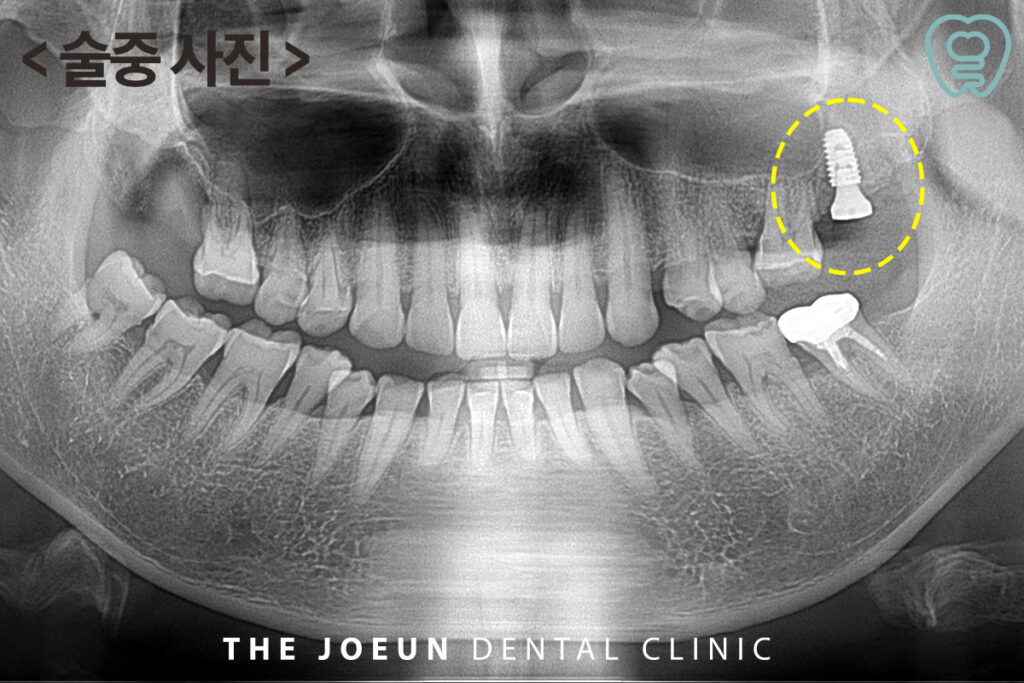

당일 발치 후 치조정 접근법을 통한 상악동 거상술을 동반하여 임플란트 식립까지 진행을 마쳤습니다.

발치 후 즉시 임플란트는 치아가 없는 기간을 줄여 치조골의 위축을 줄여주며 자연스러운 잇몸 라인을 유지할 수 있고 발치 부위 자연치유력을 이용하여 뼈의 결합을 유도하기 때문에 자연스럽게 치료비 절약 효과도 얻을 수 있습니다. 더불어 고난이도 시술인 상악동 거상술을 동반하여야 했으므로 환자분의 상태, 골의 높이, 전신 건강 상태 등을 종합적으로 판단해 결정하여야 하며 섬세한 술기가 요구되는 만큼 임상 경험이 풍부한 서재리치과 의료진과의 상담과 집도가 중요합니다.